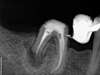

A la suite d'un kyste sous une molaire soutenant un bridge, nous avons choisit l'opération pour solutionner le problème.

Le bridge est déposé, le traitement canalaire refait, photo 2.

Dans ce cas la racine présente une forte résorption suite à l'ancien kyste.

La racine devra également être régulariser à son extrémité à la fin de l'intervention , pour éliminer les microbes vivants à sa périphérie.